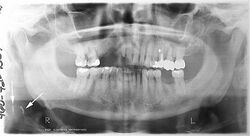

A panoramic radiograph of a 9 year old in mixed dentition